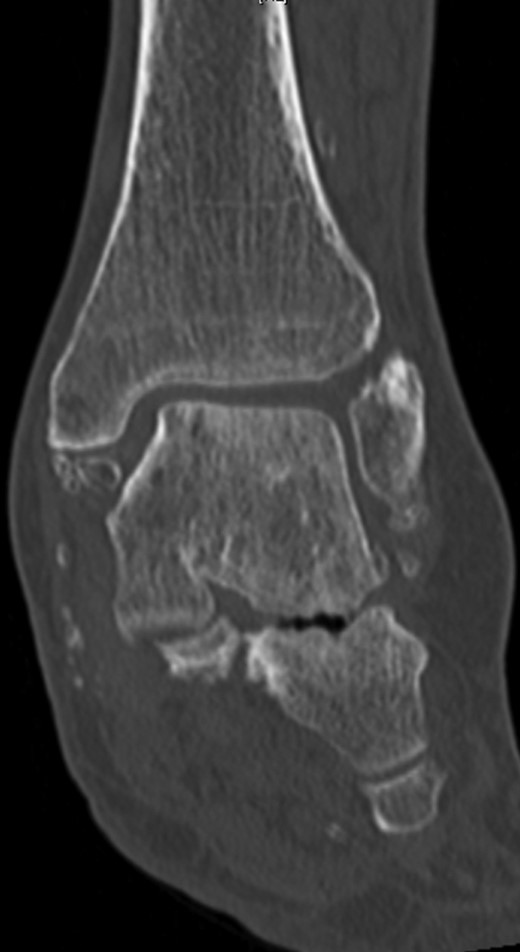

The X-ray and CT scan of the cervical spine revealed significant hyperostosis of the ventral cervical spine segments C3–C7. Hyperostosis was most extensive at segments C3–C5 causing stenosis of the pharyngeal lumen at the level of the larynx (Fig. 1). Due to accompanying joint pain, additional radiological examinations were performed. CT of the right shoulder showed extensive osseous proliferation of the medial humeral head reducing the articular space of the glenohumeral joint, as well as calcification of the rotator cuff (Fig. 2). In the left ankle, the CT scan revealed ossification of the deltoid ligament, and Kellgren grade 4 arthrosis of the tibiotalar and talocalcaneal joints (Fig. 3).

CT of the left ankle in a coronary plane. Ossification is present in the deltoid ligament. The tibiotalar and talocalcaneal joints show Kellgren grade 4 arthrosis.